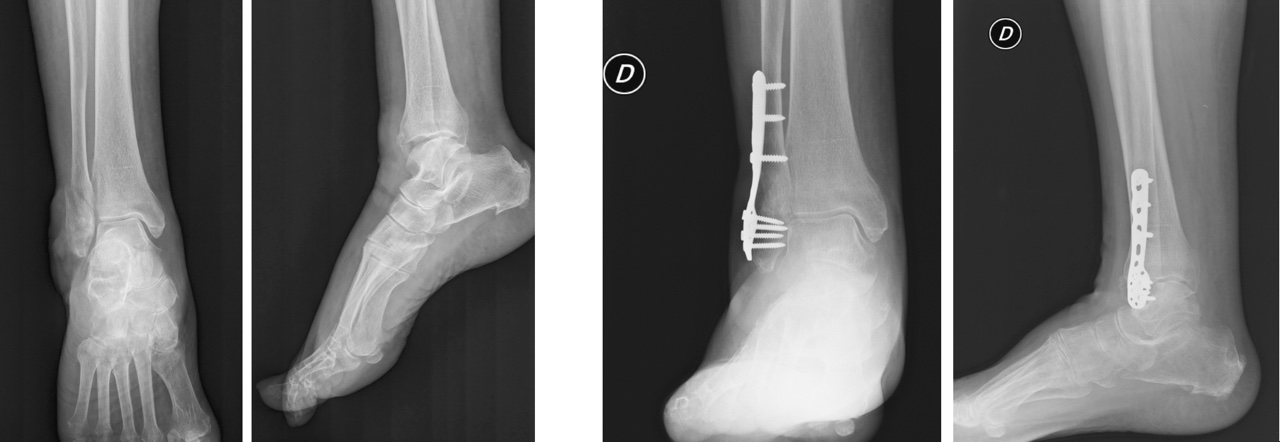

Il trattamento delle fratture malleolari sia esso conservativo o chirurgico, è fortemente condizionato dallo stato dei tessuti molli (considerare per questo motivo l’utilizzo di un FEA temporaneo), dall’obesità e nel paziente anziano anche dall’osteoporosi e da un’eventuale politerapia farmacologica. Le fratture infrasindesmosiche isolate del malleolo peroneale e stabili, possono essere trattate incruentemente. L’indicazione può divenire chirurgica in relazione all’instabilità e all’ incongruenza del mortaio in quanto tali fratture, provocando un carico anomalo sulla superficie articolare, possono portare a un quadro di artrosi precoce. La ricostruzione del perone, finalizzata al ripristino dell’asse e della corretta lunghezza, è il primo step durante l’osteosintesi delle fratture malleolari; l’utilizzo delle placche di ultima generazione, anche ad esempio con funzione di sostegno, associata a vite interframmentaria nel trattamento delle lesioni di tipo B con frattura di perone a rima obliqua corta, permette di non compromettere la vascolarizzazione periostale e raggiungere anche ad esempio in un paziente anziano un corretto bone healing. In caso però di frammento da strappo del malleolo laterale, così come nelle fratture da avulsione del malleolo tibiale (di solito in quelle di tipo B), può essere eseguita una sintesi con tirante secondo Weber. Sempre nelle fratture tipo con frattura isolata del malleolo peroneale una possibile insufficienza del legamento deltoideo è meglio diagnosticata con radiografie sotto stress o con Rx di controllo dopo 1 settimana dal trauma.

Il distacco del malleolo posteriore (nelle Tipo B), invece, può invece essere ridotto indirettamente trattando il malleolo laterale, laddove però tale frammento sia riconducibile a un tipo I secondo la classificazione TAC di Bartonıcek and Rammelt7. La raccomandazione che emerge oggi dall’analisi della letteratura è la necessità di trattare chirurgicamente il terzo malleolo allorquando il frammento sia di grandi dimensioni e coinvolge la superficie articolare: la sintesi deve ovviamente essere stabile ed eseguita a cielo aperto attraverso l’accesso postero-laterale 8.

Nelle fratture sovra-sindesmosiche (tipo C) va considerato sempre l’utilizzo di una vite di stabilizzazione della sindesmosi posizionata con piede in lieve flessione dorsale per impedire il restringimento del mortaio. Secondo la nostra esperienza, nelle fratture da fragilità, è preferibile eseguire una stabilizzazione della sindesmosi quadricorticale allorquando non venga utilizzata una fissazione dinamica poiché, in caso di rottura del mezzo di sintesi, è possibile rimuovere il frammento filettato mediante un accesso dalla corticale tibiale mediale. La fissazione statica della sindesmosi deve essere eseguita a 2 cm prossimalmente all’articolazione introducendo le viti (possibilmente due, da spongiosa 4 mm) obliquamente dalla parte posteriore a quella anteriore con un angolo di 25°-30°. La presenza di un Hook test positivo e l’allargamento dello spazio articolare visibile con scopie intraoperatorie maggiore di 2 mm indicano un’instabilità della sindesmosi e pertanto l’obbligatorietà al trattamento chirurgico.